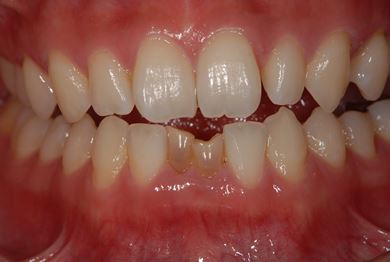

| 性別/年齢 | 女性 / 28歳 | ||||||||||||||||||||||||||||||||

| 主訴 | 下前歯の色が気になるので、ホワイトニングかセラミック治療できれいにしたい。(下前歯2本は乳歯でした) | ||||||||||||||||||||||||||||||||

| 治療方針 | 下顎前歯、乳歯を抜歯し、セラミック治療にて審美的回復を行う。 | ||||||||||||||||||||||||||||||||

| 治療内容 | エンプレスジルコニアフレームオールセラミッククラウンブリッジ4本 | ||||||||||||||||||||||||||||||||